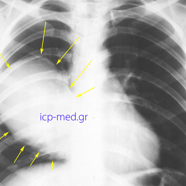

IMAGES 1-6: Gigantic Hydatid Cyst of the right lung in a 19-yo male smoker's case (preop imaging investigations).